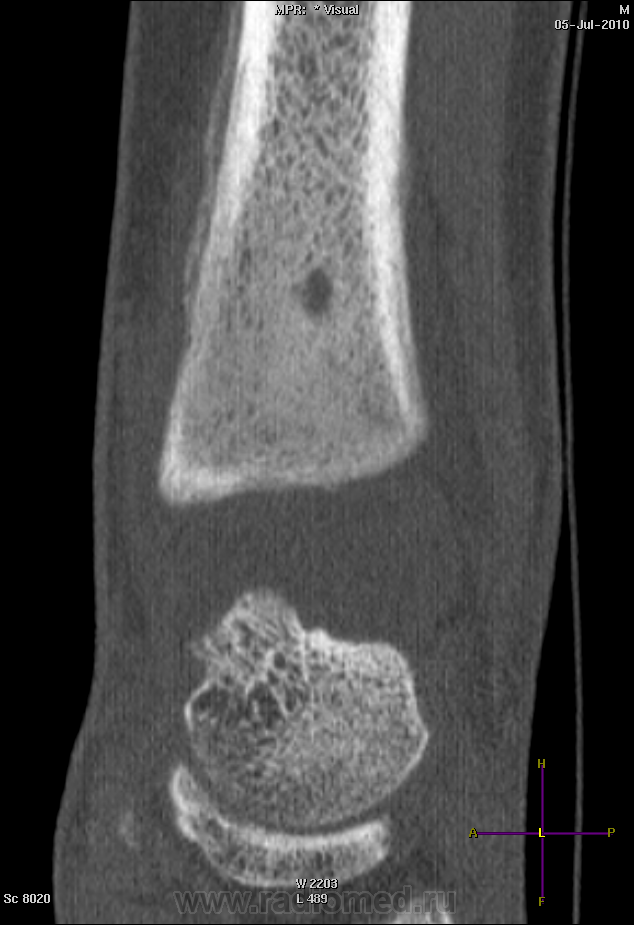

А, вот еще "братики - Бродики"